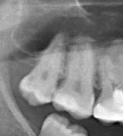

Zenden Опубликовано 19 декабря, 2013 Поделиться Опубликовано 19 декабря, 2013 (изменено) Всем добрый день, вот такой вопрос: Месяц назад лечил верхнюю восьмерку, по словам врача средний кариес. После пломбировки зуб, до этого никак не беспокоивший, стал чувствительным. Холодное-горячее, больно жевать (при нажатии). Но при этом если зуб не беспокоить, то и он не болит и никак про себя не напоминает. Причем есть еще одна особенность: со стороны щеки зуб реагировал особенно сильно - даже на проведение пальцем! Зато со всех остальных сторон никакой реакции. Сейчас, через месяц после лечения, чувствительность на холодное-горячее осталась, но стала меньше и "тупее". Но и полностью не прошла. И вот на днях я лечил верхнюю восьмерку с другой стороны (средний кариес). И все опять то же самое! Опять зуб никак не беспокоил до лечения, зато теперь реагирует на все подряд! И особенно со стороны щеки! Посоветуйте что делать в такой ситуации - мой врач сказал, что это нормально, и зубы могут до 5 месяцев быть чувствительными. Это действительно так? И почему повышенная чувствительность именно со стороны щеки? Изменено 19 декабря, 2013 пользователем Zenden Ссылка на комментарий

red_butler Опубликовано 19 декабря, 2013 Поделиться Опубликовано 19 декабря, 2013 Антагонисты ( зубы мудрости внизу) отсутствуют, дистопия/ экструзия восьмых зубов (выдвигаются).Отпустите свои зубы мудрости, не тратьте время и средства 1 Ссылка на комментарий